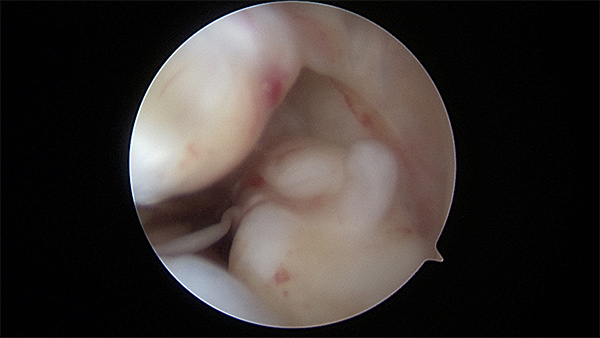

Arthroscopic view of a normal ACL in a 22 year old male (image courtesy of Dr. Eric Makhni)